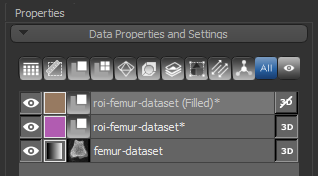

At the end of the process, a new region of interest (Filled) will appear in the Data Properties and Settings panel.

- Click Next to continue to the next segmentation step.

Segmentation of the cortical and trabecular bone is the most critical step for the accurate quantification of selected morphometric indices. Two methods — Kohler and Buie — are available for segmenting cortical and trabecular bone. The input of the automated segmentation is a bone segmentation in which bone mineralization is present (see Performing Initial Bone Segmentations) and a filled region of interest in which the bone segmentation are filled. The output of the process is two regions of interest listed below:

At the end of the process, two new regions of interest — Cortical bone and Trabecular bone — appear in the Data Properties and Settings panel.